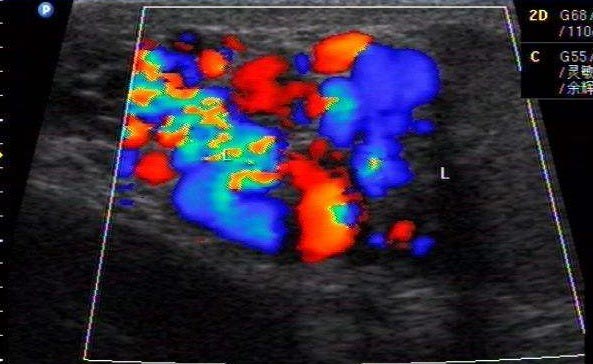

精索靜脈曲張的患者常常由于缺乏自覺癥狀而得不到及時診治,最終導(dǎo)致部分患者生精能力受損。少數(shù)患者可有立位時陰囊腫脹,陰囊局部持續(xù)間歇墜脹疼痛感、隱痛和鈍痛,可向下腹部,腹股溝區(qū)或后腰部放射,勞累或久站后及行走時癥狀加重,平臥休息后癥狀減輕或消失。對有以上癥狀的男士可以進(jìn)行彩色多普勒血流顯像。對精液常規(guī)檢查示精子密度低,活率,活力低,畸形率高的患者,均建議進(jìn)行彩色多普勒血流顯像儀(CDFI)檢查,CDFI可直觀,準(zhǔn)確的觀察精索靜脈曲張的擴(kuò)張程度,血流狀態(tài),是目前無創(chuàng)、準(zhǔn)確的診斷途徑。